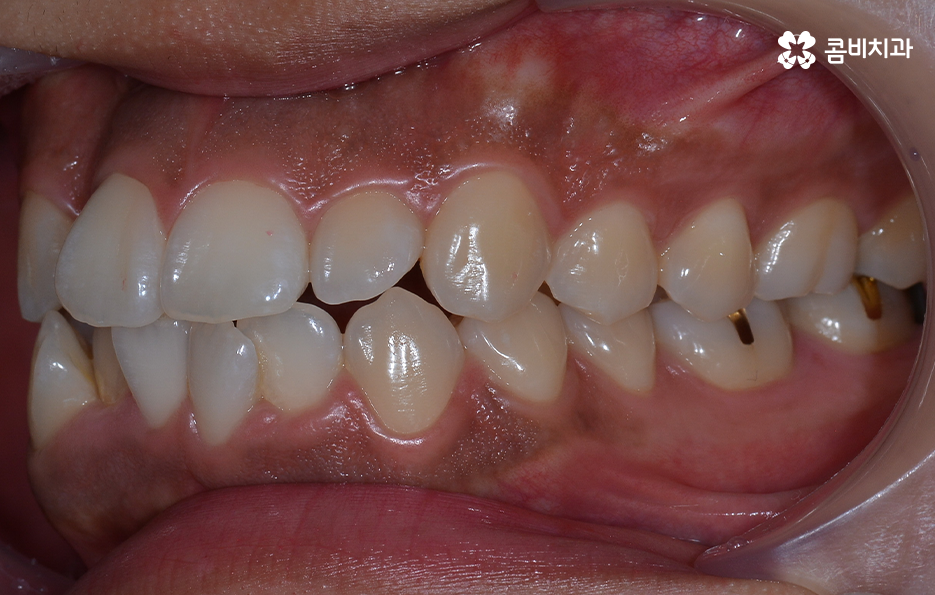

앞니의 덧니가 심하고 겹쳐 있는 경우에는 교합이 제대로 맞물리지 않거나 이물질이 치아 사이에 끼기 쉽고 그로 인해 치석이 쌓이기 때문에 나이가 들수록 덧니를 방치할 경우 충치 뿐 아니라 치주질환의 가능성이 높아지고 있는데요

덧니 교정을 통해서 치아 교합의 기능적 개선과 치아 관리의 용이성 높일 수 있고 치아 건강에도 도움이 되며 심미적인 개선도 도움이 될 수 있어요

심한 덧니로 고민하시는 분들은 환하게 웃고 싶지만 입을 가리고 웃는다거나 돌출입으로 인해 가만히 있어도 입이 벌어지는 등의 불편함을 느끼시는 분들이 많기 때문에 치아교정을 통한 치열의 개선 뿐 아니라 자신감의 향상, 얼굴 외형적인 변화까지 얻을 수 있기 때문에 그만큼 정확한 검진과 치료 예측을 통해 치아교정 계획을 잘 세우는 것이 그만큼 중요할 거예요